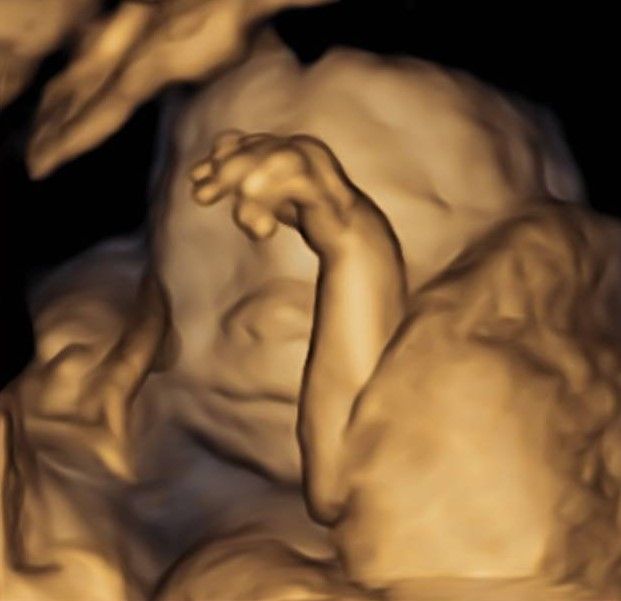

Eseguo in particolare ecografie ostetriche e ginecologiche anche in 3D e 4D per meglio identificare la problematica, offrire diagnosi precise ed un trattamento mirato e personalizzato.